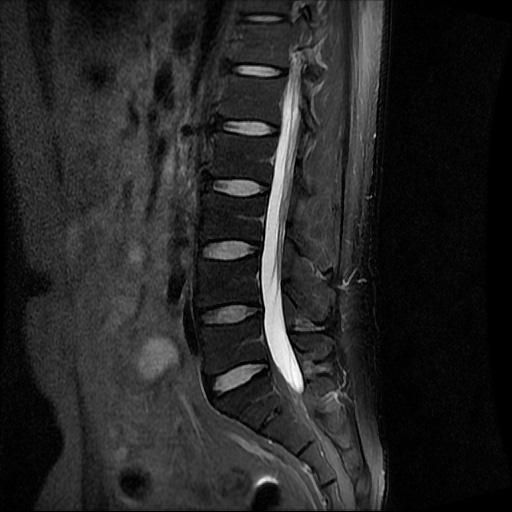

허리 MRI 전문가분들 의견부탁드립니다.

이번에 허리 MRI찍었는데

상태 어떤지 고견 여쭙습니다.

눕다싶이 앉은 자세 혹은 책상위에 다리 올려서 컴퓨터 하는 습관이 있었는데 왼쪽 허리가 아파서요.

큰 이상이나 문제점은 없어 보이는 것으로 생각되는데요, 허리통증이 지속되는 경우에는 반드시 디스크 질환에 의한것은 아닐 수 있습니다.

MRI상에 보기에는 큰문제는 없어보이는데요 하지만 MRI상에 문제가없다고하더라도 환자에따라 통증이 심할수있는데요 지속적으로 불편감이있다면 병원에서 치료를받아보시길 바랍니다

현재로썬 디스크 상태는 심하지않는것으로 확인이 됩니다.